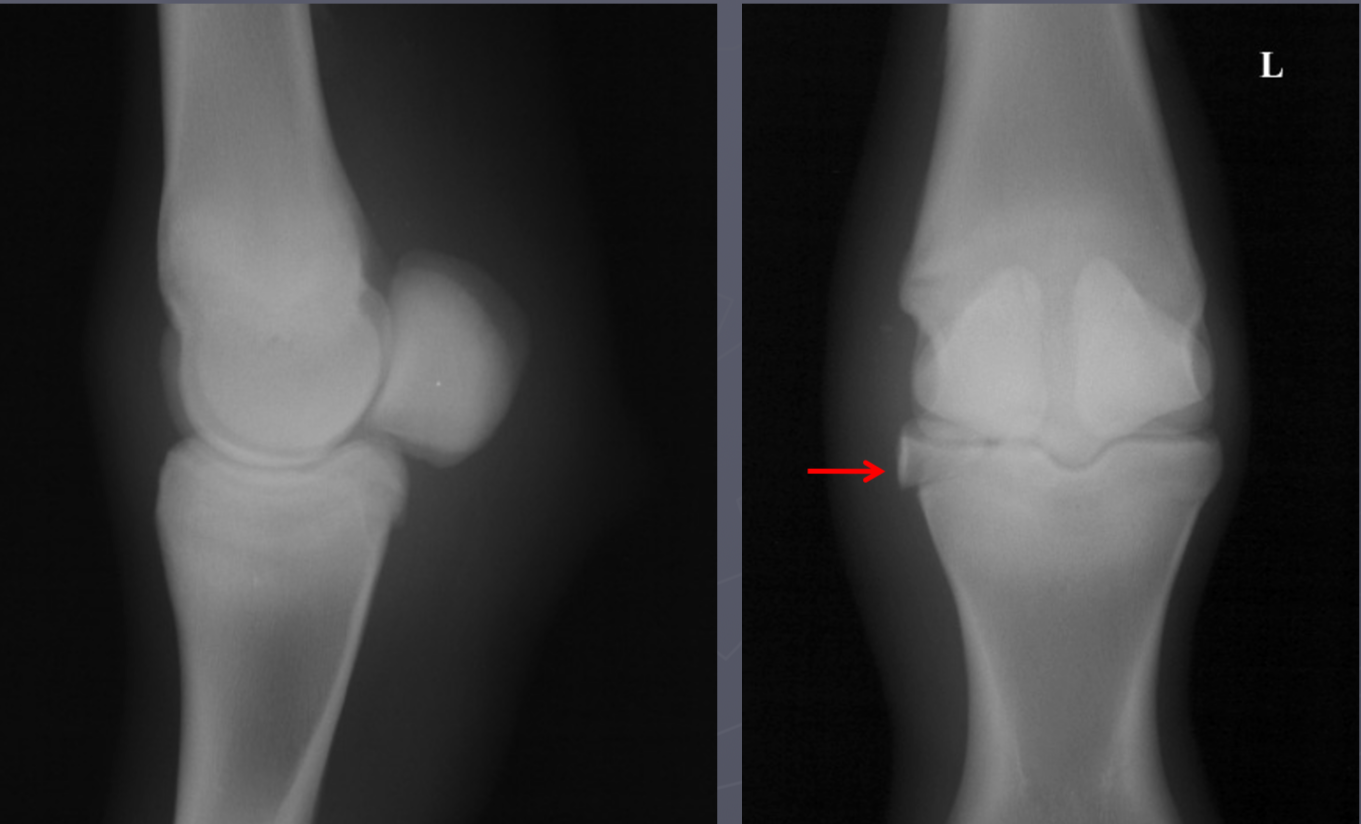

which OCD lesions are these in the dog

A = cd humerus

B = medial humeral condyle (elbow)

C = medial trochlear ridge (ankle)

D =lateral femoral condyle (knee)